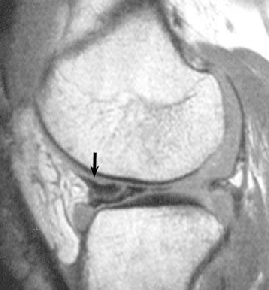

• ACL 손상 방사선 사진2